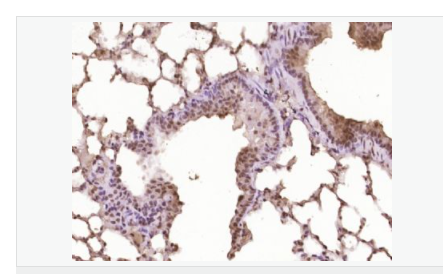

| 產品應用 | WB=1:500-2000 ELISA=1:5000-10000 IHC-P=1:100-500 IHC-F=1:100-500 Flow-Cyt=1ug/Test ICC=1:100-500 IF=1:100-500 (石蠟切片需做抗原修復) not yet tested in other applications. optimal dilutions/concentrations should be determined by the end user. |

| 細胞定位 | 細胞核 |

| 產品介紹 | This gene encodes a member of the Notch family. Members of this Type 1 transmembrane protein family share structural characteristics including an extracellular domain consisting of multiple epidermal growth factor-like (EGF) repeats, and an intracellular domain consisting of multiple, different domain types. Notch family members play a role in a variety of developmental processes by controlling cell fate decisions. The Notch signaling network is an evolutionarily conserved intercellular signaling pathway which regulates interactions between physically adjacent cells. In Drosophilia, notch interaction with its cell-bound ligands (delta, serrate) establishes an intercellular signaling pathway that plays a key role in development. Homologues of the notch-ligands have also been identified in human, but precise interactions between these ligands and the human notch homologues remain to be determined. This protein is cleaved in the trans-Golgi network, and presented on the cell surface as a heterodimer. This protein functions as a receptor for membrane bound ligands, and may play multiple roles during development. [provided by RefSeq, Jul 2008]. Function: Notch family members play a role in a variety of developmental processes by controlling cell fate decisions. The Notch signaling network is an evolutionarily conserved intercellular signaling pathway which regulates interactions between physically adjacent cells. The protein is cleaved in the trans-Golgi network, and presented on the cell surface as a heterodimer. This protein functions as a receptor for membrane bound ligands. Once the Notch extracellular domain interacts with a ligand, a protease called TACE (Tumor Necrosis Factor Alpha Converting Enzyme) cleaves the Notch protein just outside the membrane. This releases the extracellular portion of Notch, which continues to interact with the ligand. The ligand plus the Notch extracellular domain is then endocytosed by the ligand expressing cell. After this first cleavage, an enzyme called gamma-secretase cleaves the remaining part of the Notch protein just inside the inner leaflet of the cell membrane. This releases the intracellular portion of the Notch protein, which then moves to the nucleus and causes various genes to be expressed. There are many other proteins involved in the intracellular portion of the Notch signalling cascade. Subunit: Heterodimer of a C-terminal fragment N(TM) and an N-terminal fragment N(EC) which are probably linked by disulfide bonds. Interacts with DNER, DTX1, DTX2 and RBPJ/RBPSUH. Also interacts with MAML1, MAML2 and MAML3 which act as transcriptional coactivators for NOTCH1. The activated membrane-bound form interacts with AAK1 which promotes NOTCH1 stabilization. Forms a trimeric complex with FBXW7 and SGK1. Interacts with HIF1AN. HIF1AN negatively regulates the function of notch intracellular domain (NICD), accelerating myogenic differentiation. Subcellular Location: Cell membrane; Single-pass type I membrane protein. Notch 1 intracellular domain: Nucleus. Note=Following proteolytical processing NICD is translocated to the nucleus. Tissue Specificity: In fetal tissues most abundant in spleen, brain stem and lung. Also present in most adult tissues where it is found mainly in lymphoid tissues. Post-translational modifications: Synthesized in the endoplasmic reticulum as an inactive form which is proteolytically cleaved by a furin-like convertase in the trans-Golgi network before it reaches the plasma membrane to yield an active, ligand-accessible form. Cleavage results in a C-terminal fragment N(TM) and a N-terminal fragment N(EC). Following ligand binding, it is cleaved by TNF-alpha converting enzyme (TACE) to yield a membrane-associated intermediate fragment called notch extracellular truncation (NEXT). Following endocytosis, this fragment is then cleaved by presenilin dependent gamma-secretase to release a notch-derived peptide containing the intracellular domain (NICD) from the membrane (By similarity). Phosphorylated (By similarity). O-glycosylated on the EGF-like domains. Contains both O-linked fucose and O-linked glucose. Ubiquitinated; undergoes 'Lys-29'-linked polyubiquitination catalyzed by ITCH. Monoubiquitination at Lys-1759 is required for activation by gamma-secretase cleavage, it promotes interaction with AAK1, which stabilizes it. Deubiquitination by EIF3F is necessary for nuclear import of activated Notch. Hydroxylated at Asn-1955 by HIF1AN. Hydroxylated at Asn-2022 by HIF1AN (By similarity). Hydroxylation reduces affinity for HI1AN and may thus indirectly modulate negative regulation of NICD. DISEASE: Defects in NOTCH1 are a cause of aortic valve disease 1 (AOVD1) [MIM:109730]. A common defect in the aortic valve in which two rather than three leaflets are present. It is often associated with aortic valve calcification and insufficiency. In extreme cases, the blood flow may be so restricted that the left ventricle fails to grow, resulting in hypoplastic left heart syndrome. Similarity: Belongs to the NOTCH family. Contains 5 ANK repeats. Contains 36 EGF-like domains. Contains 3 LNR (Lin/Notch) repeats. SWISS: P46531 Gene ID: 4851 Database links: Entrez Gene: 4851 Human Entrez Gene: 18128 Mouse Omim: 190198 Human SwissProt: P46531 Human SwissProt: Q01705 Mouse Unigene: 495473 Human nigene: 290610 Mouse Important Note: This product as supplied is intended for research use only, not for use in human, therapeutic or diagnostic applications. |